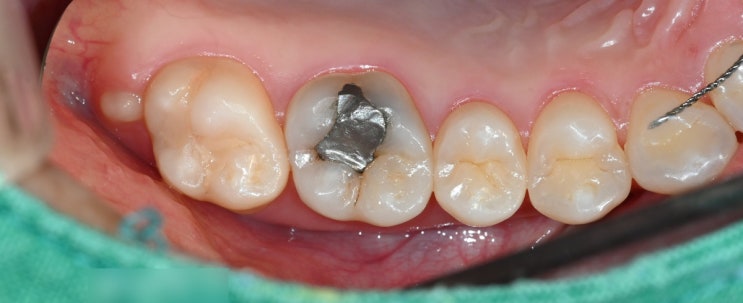

신촌역 치과 오래된 아말감 치아 2차 충치 개선과 유지장치(픽스드) 끊어짐 인레이, 크라운, 레진 치료

안녕하세요. 조민기입니다. 이제 올해 마지막 달만 남았습니다. 여러분들께서는 올해 초 목표했던 것들은 ...